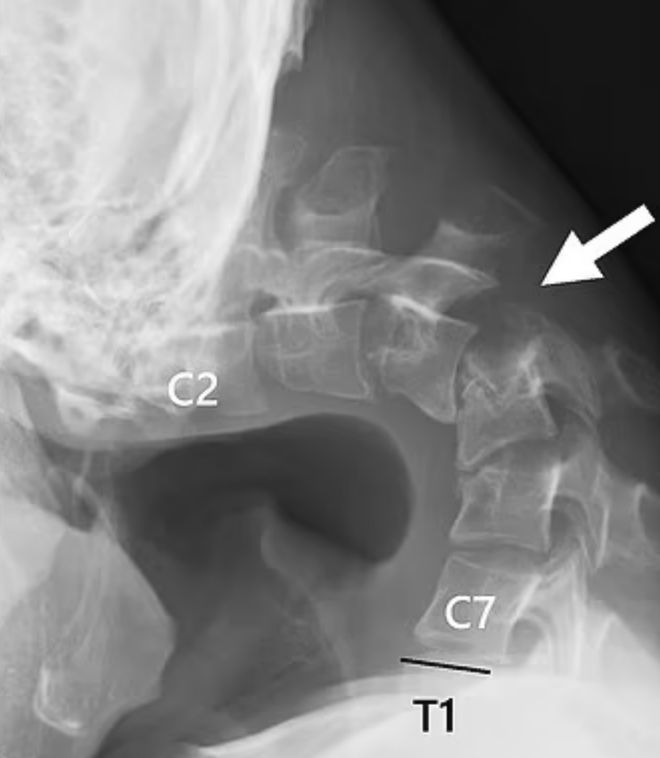

据悉,患者为一名25岁男子,患者家属同意医生公布其具体患病细节,以警示更多人。照片显示,患者的后颈部出现了一个非常尖锐的肿块,医生认为这是由于他的椎骨因不自然的位置而“极度伸展”造成的。

医院的扫描结果显示,他的颈椎已经变形脱臼,随着时间的推移,脊柱中形成了类似疤痕的组织。